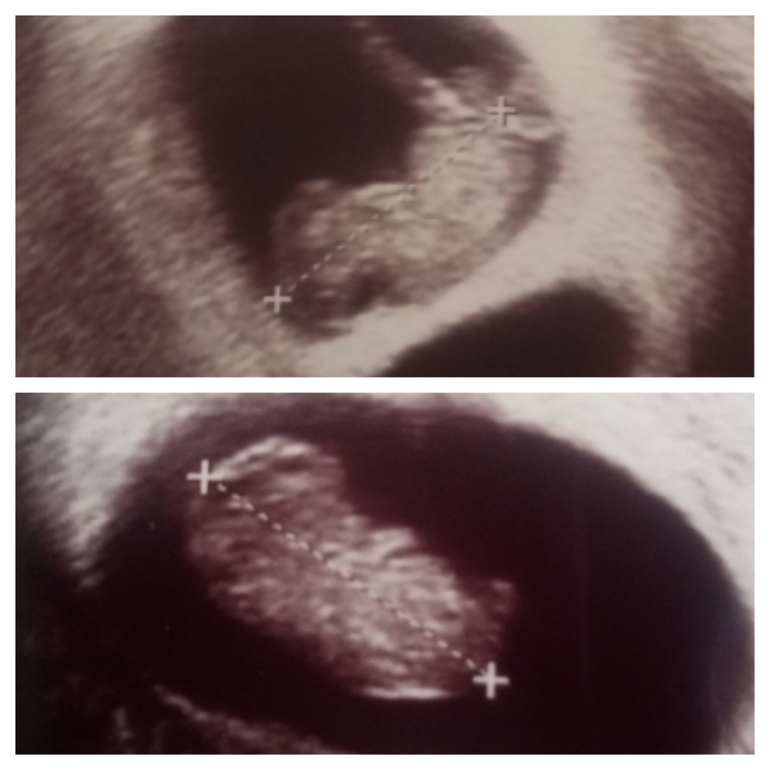

Нам 9 недель. Как же быстро летит время. Фото малышей....

Мы уже совсем большие ))) 2 см 38 мм и 2 см 37 мм. Один малыш точно как мой сынуля в этот момент. А второй малыш совсем другой. Может это и есть та самая девчушка 😉